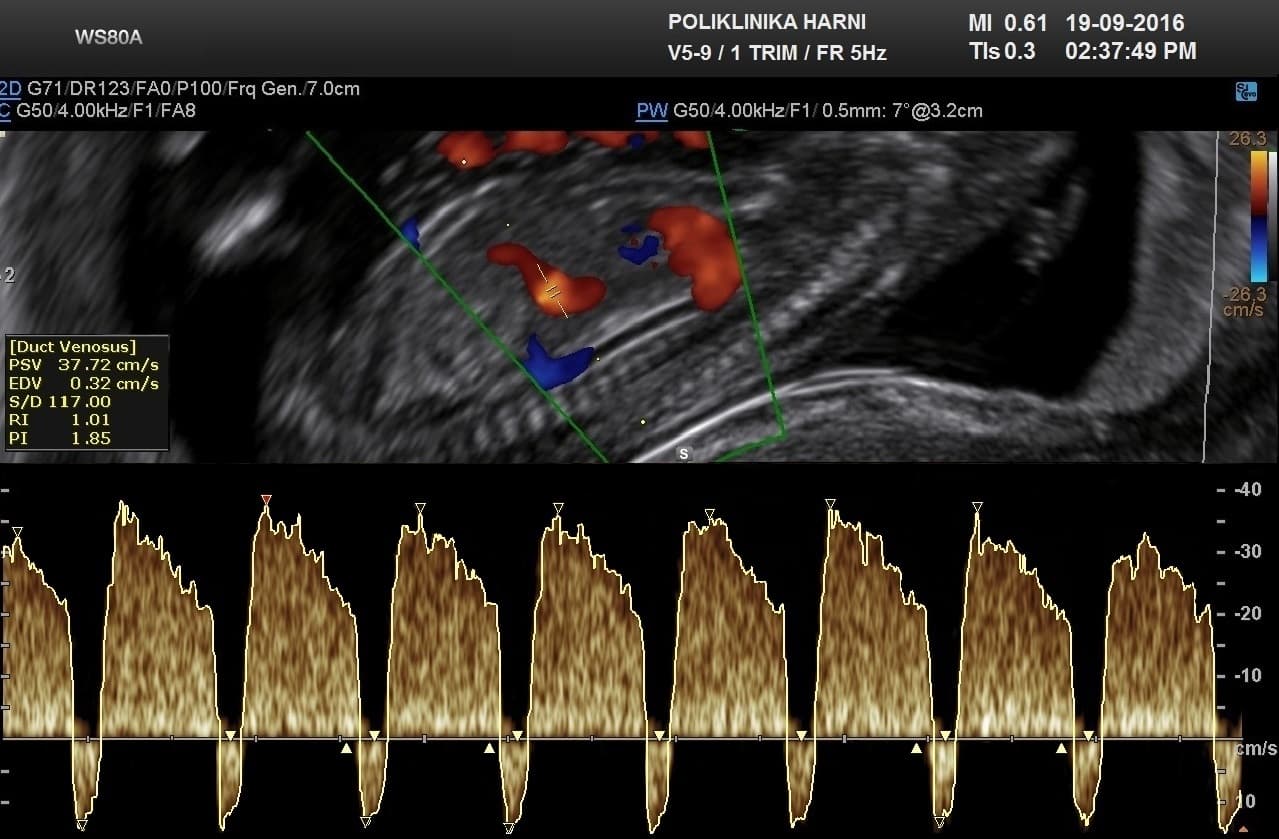

Radi se o specifičnim ultrazvučnim pokazateljima koji ne spadaju u anomalije već prije prolazne pojave u trudnoći. Obuhvaćaju ne samo debljinu nuhalnog nabora, već i prisutnost nosne kosti, lični kut, nalaz dvije umbilikalne arterije, procjenu protoka kroz duktus venozus tijekom atrijske kontrakcije i nalaz trikuspidalne regurgitacije. Procjenjuju se prema strogim kriterijima koje je propisao FMF – Fetal Medicine Foundation, London, između 11. i 13+6 tjedna trudnoće kada je duljina tjeme-trtica između 45 - 84 mm. Ovaj ultrazvučni pregled je poznat i pod nazivom mini-anomaly scan.